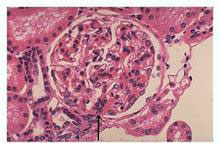

急性肾衰竭(ARF)

疾病介绍:急性肾衰竭(ARF)是指肾小球滤过功能在数小时至数周内迅速降低而引起的以水、电解质和酸碱平衡失调以及氮质代谢产物蓄积为主要特征的一组临床综合症,…【详细】